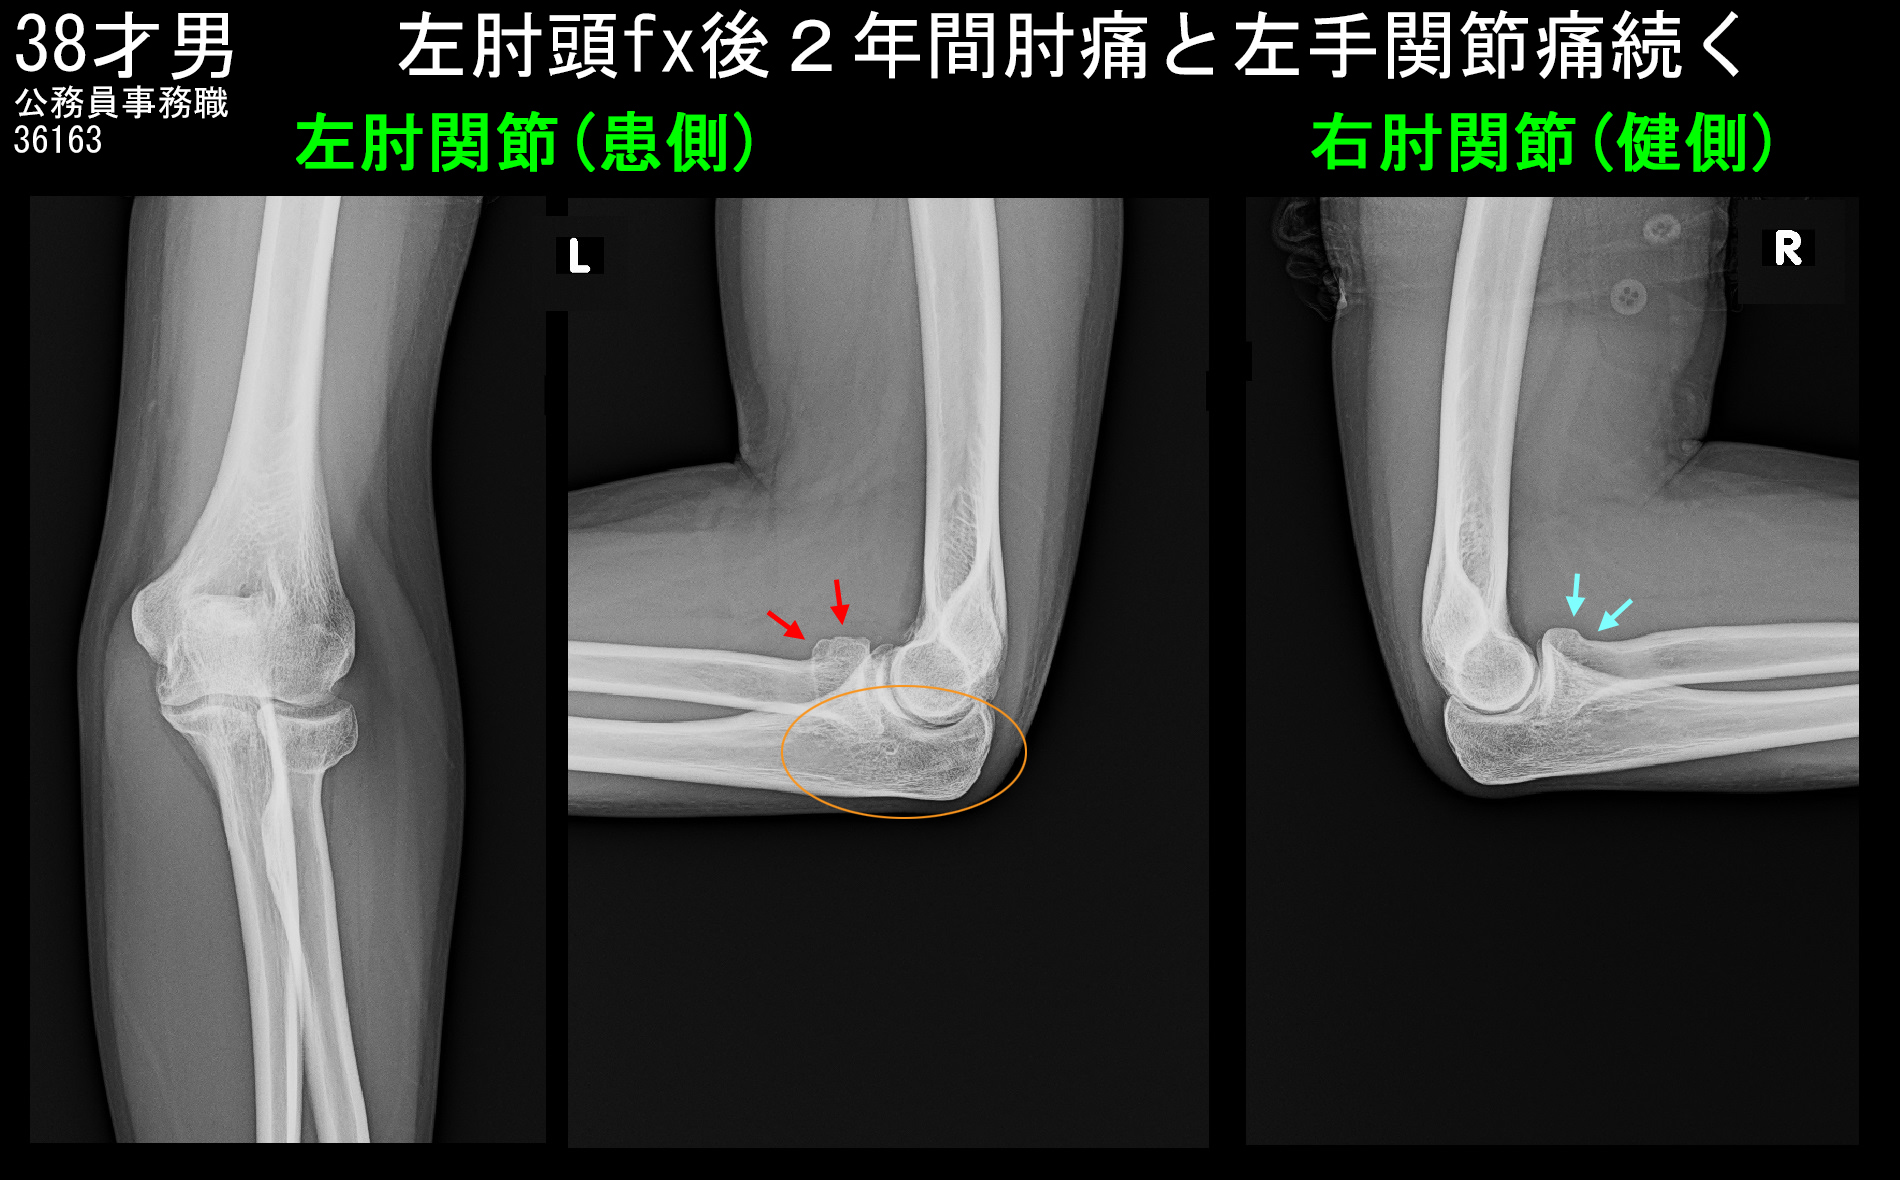

38才男MRI3.jpg

MRIでの尺骨肘頭部は赤矢印で関節面が軽微断裂または段違いとなっていますが、このような軽微な所見は通常のレントゲン像では正常と認識されることが大半です。受傷時の肘頭骨折がこれだけの所見だったのか、もっと違う所見があったのかは分かりません。

左肘は橈骨頭部のところで関節面が段違いとなり、日常の使用により関節軟骨が摩耗して、変形性関節症化しつつある状態と理解されます。2年間続いた痛みの原因である軟骨摩耗による関節炎の軽減に対して最も有効なのは関節内注射の治療であると私は考えるため、関節内注射を提案したところ、患者さんは了承されました。